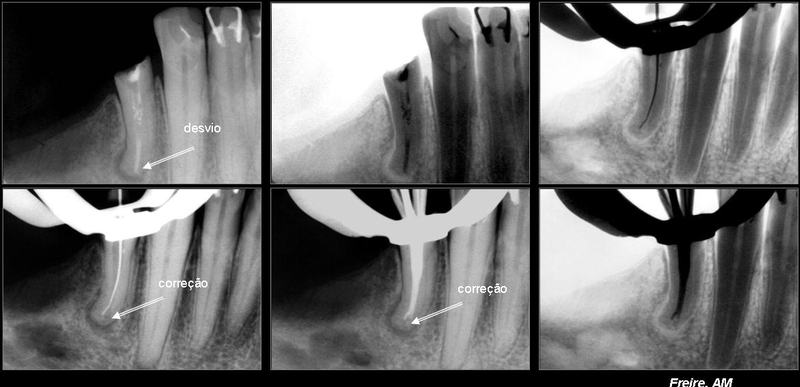

Casos clínicos com Controle radiográfico.